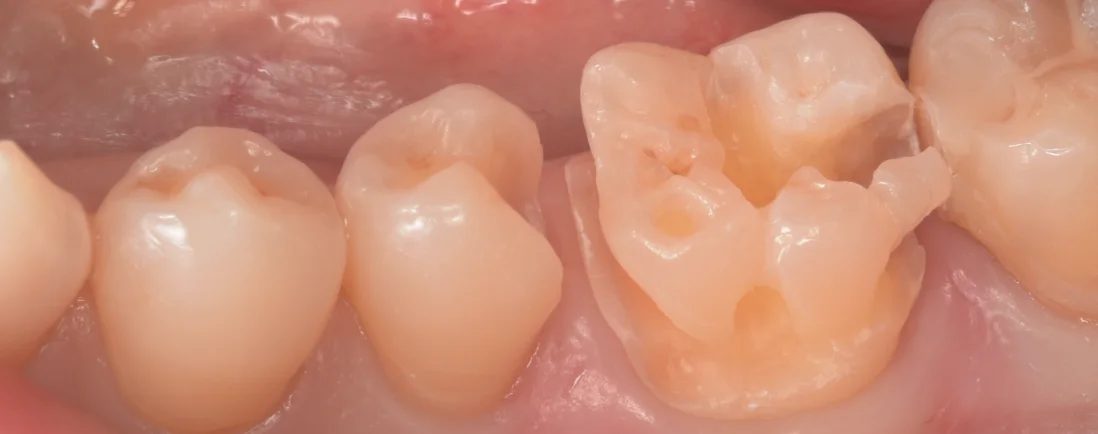

このくらいのサイズでした。

歯の多くがすでに虫歯でなくなってしまってました。

ただ、幸いなことに失うと被せ物に発展せざるを得ない「咬頭」の部分がほとんど残っているため、そのまま詰め物で対応できる状況でした。

前回の治療の段階で前医がレジンではなく型取りをするタイプの詰め物を選択していたら私でも今回のは全周大きく削る被せ物にせざるを得ない状況だったと思います。

やはり初回の歯の治療をどこの歯科医院で受けるのかはその人の歯を残す上で非常に大きなファクターだと改めて実感したケースでした。